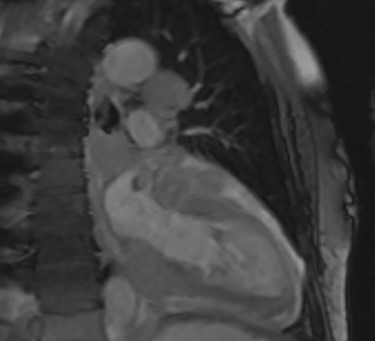

Intraoperatively, he developed new t-wave inversion on lead II of the 3-lead electrocardiogram (ECG). This resolved post-operatively, and he denied chest pain. He was kept in overnight for observation. The next morning, during the round, he reported central crushing chest pain the previous day that he had not disclosed. His ECG was repeated and demonstrated the t-wave inversion in lead II—indicating dynamic ECG changes. A troponin I level measured 27. As such, management for a non-ST elevation myocardial infarction was initiated and a cardiology consult organized, who advised continued acute coronary syndrome (ACS) treatment and an echocardiogram. This demonstrated a ‘pericardial mass (subcostal 3 cm × 2.5 cm) encroaching and extending outwards on both sides of the right atrioventricular groove’. ACS protocol was stopped and a cardiac magnetic resonance imaging (MRI) was organized (Figs 2 and 3).

Cardiac MRI (transverse plane) demonstrating an enhancing lesion surrounding the chambers of the heart.

This demonstrated a bulky mediastinal tissue (measuring 50% of the heart) that encased all the aorta and pulmonary artery as well as the coronary artery. It has malignant behaviour with multiple foci that breached fascial planes. It restricted the long axis of the heart but was not causing haemodynamic occlusion. It was non-resectable.

Cardiac MRI (sagittal plane) showing the lesion encasing the aorta, pulmonary artery and all coronary arteries of the heart.